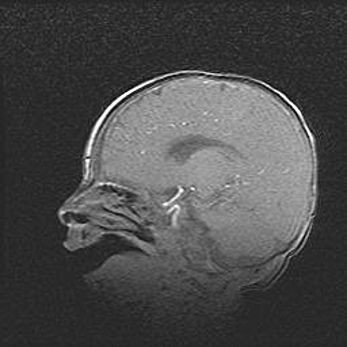

Открытая гидроцефалия.

Возраст: 9 месяцев 12 дней

Вес: 6800 г

Пол: мужской

Окружность головы: 41,5 см

Срок гестации: 28 недель

Гидроцефалия головного мозга у новорожденных имеет характерный признак: опережающий рост окружности головы приводит к визуально хорошо определяемой гидроцефальной форме сильно увеличенного в объёме черепа. Детские неврологи определяют следующие симптомы гидроцефалии у грудничков: выбухающий напряжённый родничок, частое запрокидывание головы, смещение глазных яблок к низу.